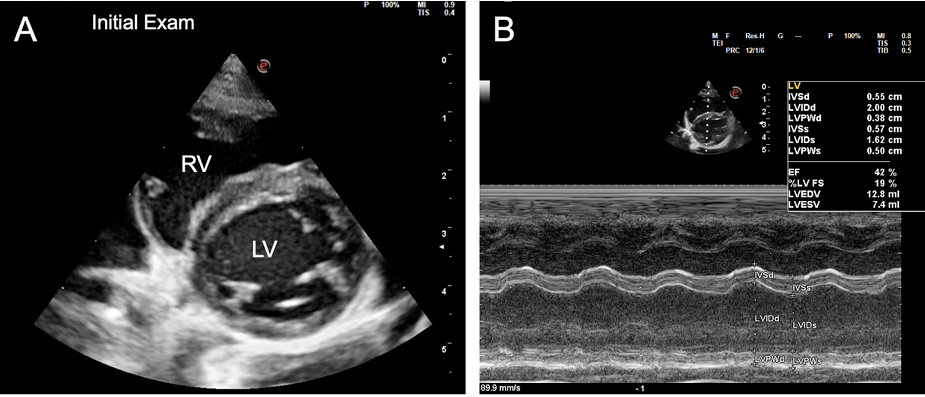

- 치료 후 심장 기능의 회복: 심부전 치료와 항생제 치료를 시작한 후, 2.5개월, 5개월, 9개월 차에 진행된 추적 심장 초음파 검사에서 놀라운 변화가 관찰되었습니다. 확장되었던 심방과 심실의 크기가 정상 범위로 줄어들고, 저하되었던 심실 수축 기능 또한 정상으로 회복되는 '역 리모델링(reverse remodeling)'이 명확하게 확인되었습니다.

- 약물 치료 중단: 5개월 차 추적 검사 후 이뇨제와 항혈전제를 중단하였고, 9개월 차에는 심장 기능이 안정적으로 유지됨에 따라 강심제인 피모벤단까지 모두 중단할 수 있었습니다. 모든 심장 약물을 중단한 후에도 고양이는 임상 증상 없이 양호한 상태를 유지했습니다.